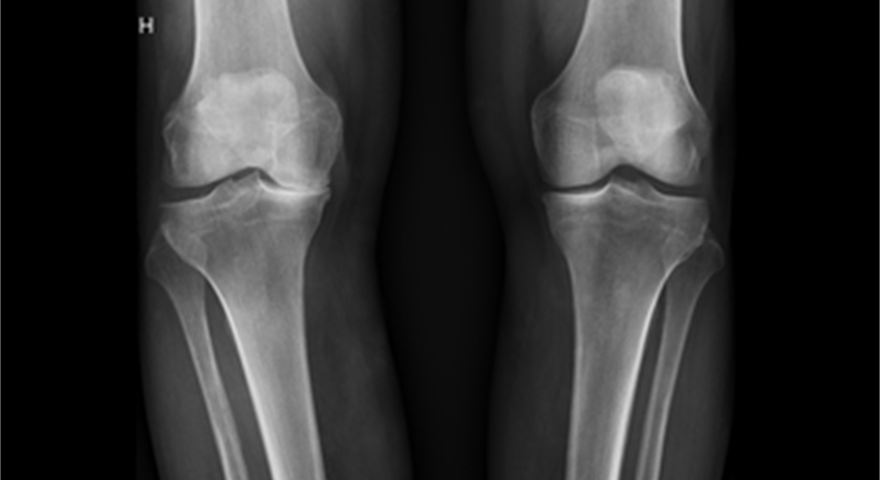

Dei nedslitte leddflatene skaper kraftig irritasjon i leddet. Dette fører til smerte og hevelse. Hevelsen skuldast at det irriterte kneleddet danner meir leddvæske enn normalt. Etter kvart som artrosen auker, kan sjølve leddet forandra seg. Det dannar seg beinpåleiringar og forkalkningar, ein kan bli hjulbeint eller kalvbeint. Slitasjen må ikkje nødvendigvis omfatta heile kneet. Ofte vil berre delar av leddet utvikla slike forandringar.